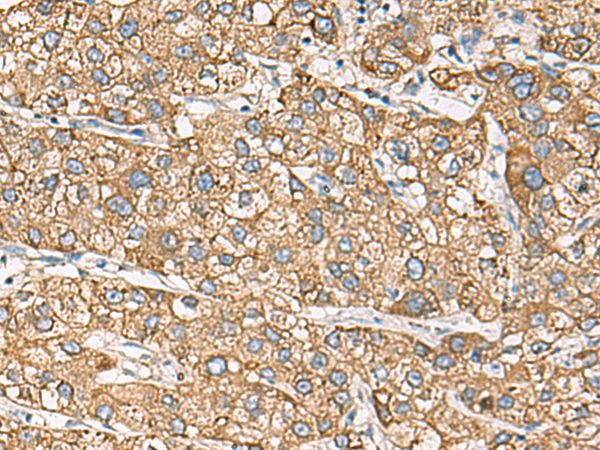

分类: 科研抗体货号: P13149别名: HB1; HB2; HH1; IVF; VF1; HBBD; ICCD; LQT3; SSS1; CDCD2; CMD1E; CMPD2; PFHB1; Nav1.5应用: IHC反应种属: Human, Mouse, Rat